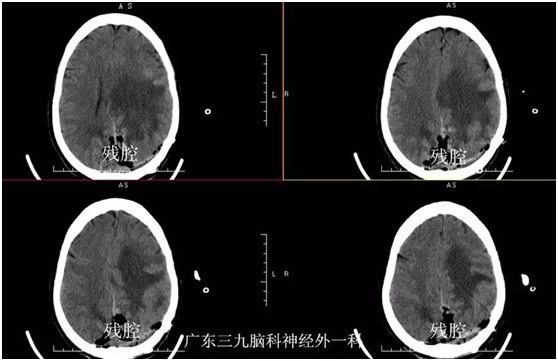

黄奶奶,72岁,因“视物模糊3个月,右侧肢体乏力半个月”入院。3个月前老奶奶无明显诱因下,出现左眼视物模糊,近半个月来出现右侧肢体乏力伴行走不稳,当地医院颅脑MR检查示:左侧枕叶镰窦旁占位性病变,门诊拟“左侧枕叶镰窦旁脑膜瘤”收入我院。入院视力1米数指。入院后完善相关检查,在全麻下行左侧枕叶镰窦旁脑膜瘤切除,手术后恢复良好,老奶奶视物较前改善,能下地行走。

视野缺损。甚至失明:脑膜瘤位于大脑后部时,可以引起视野改变,常未引起病人注意。检查可发现视野缺损。肿瘤常长到巨大体积时,巨大镰旁脑膜瘤可压迫双侧枕叶距状裂,造成失明。本例患者肿瘤正好压迫皮质视感觉区,出现视力严重下降。